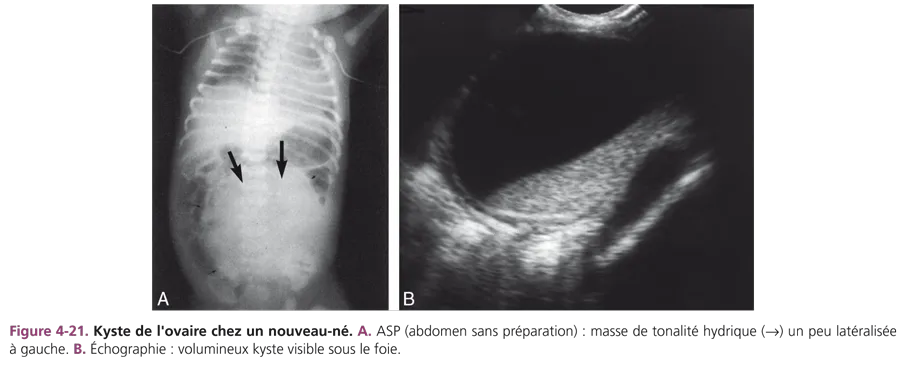

Kyste de l’ovaire

Chez un nouveau-né de sexe féminin, une masse liquidienne est un kyste de l’ovaire jusqu’à preuve du contraire. L’échographie est pratiquée pour confirmer un diagnostic anténatal ou pour étudier une masse abdominopelvienne palpée, ces kystes pouvant être très volumineux. Cliniquement, les kystes ovariens sont souvent latéralisés et mobiles, de topographie abdominopelvienne ou parfois abdominale, controlatérale à la situation d’origine. Il s’agit de kystes folliculaires simples, liquidiens, transsonores, à parois fines, de taille variable. Si le kyste est supérieur à 4 cm, le risque de torsion incite à pratiquer une ponction en période anténatale ou à la naissance (fig. 4-21).